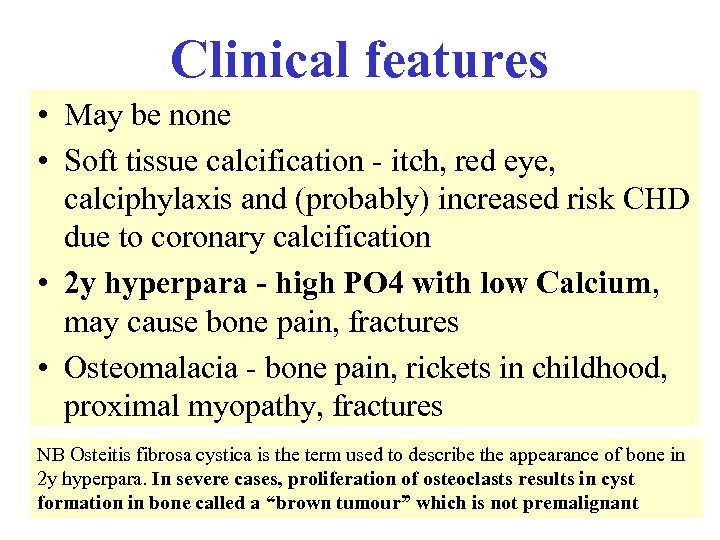

Clinical features • May be none • Soft tissue calcification - itch, red eye, calciphylaxis and (probably) increased risk CHD due to coronary calcification • 2 y hyperpara - high PO 4 with low Calcium, may cause bone pain, fractures • Osteomalacia - bone pain, rickets in childhood, proximal myopathy, fractures NB Osteitis fibrosa cystica is the term used to describe the appearance of bone in 2 y hyperpara. In severe cases, proliferation of osteoclasts results in cyst formation in bone called a “brown tumour” which is not premalignant

Clinical features • May be none • Soft tissue calcification - itch, red eye, calciphylaxis and (probably) increased risk CHD due to coronary calcification • 2 y hyperpara - high PO 4 with low Calcium, may cause bone pain, fractures • Osteomalacia - bone pain, rickets in childhood, proximal myopathy, fractures NB Osteitis fibrosa cystica is the term used to describe the appearance of bone in 2 y hyperpara. In severe cases, proliferation of osteoclasts results in cyst formation in bone called a “brown tumour” which is not premalignant